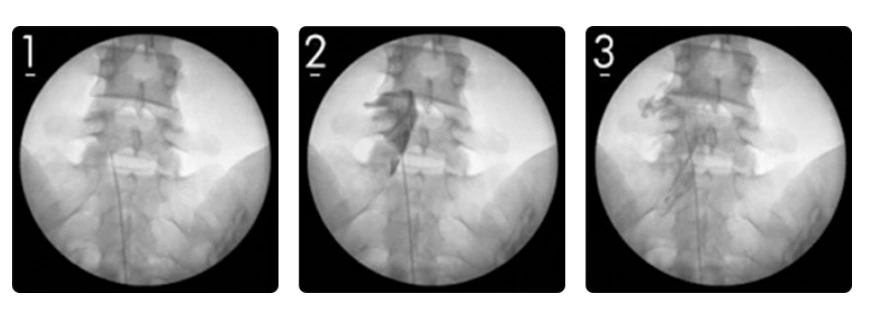

우선 국소마취를 시행한 후에 C-Arm을 통한 X-ray 투시장치로 병변을 직접 보면서 꼬리뼈 사이로 특수 카테터를 삽입합니다. 그리고 카테터가 정확한 병변에 접근하도록 하고 고농도 식염수와 유착 방지제 등 치료할 수 있는 특수약물을 주입하지요.

이렇게 미세한 카테터로 정확하게 병변에 약물을 주입하는 허리신경성형술을 하려면 풍부한 임상경험을 가진 전문의와 정확한 병변을 확인하는 검사장비와 치료장비가 필수입니다.